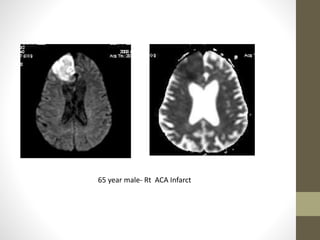

65 year male- Rt ACA Infarct

65 year male-Rt ACA Infarct